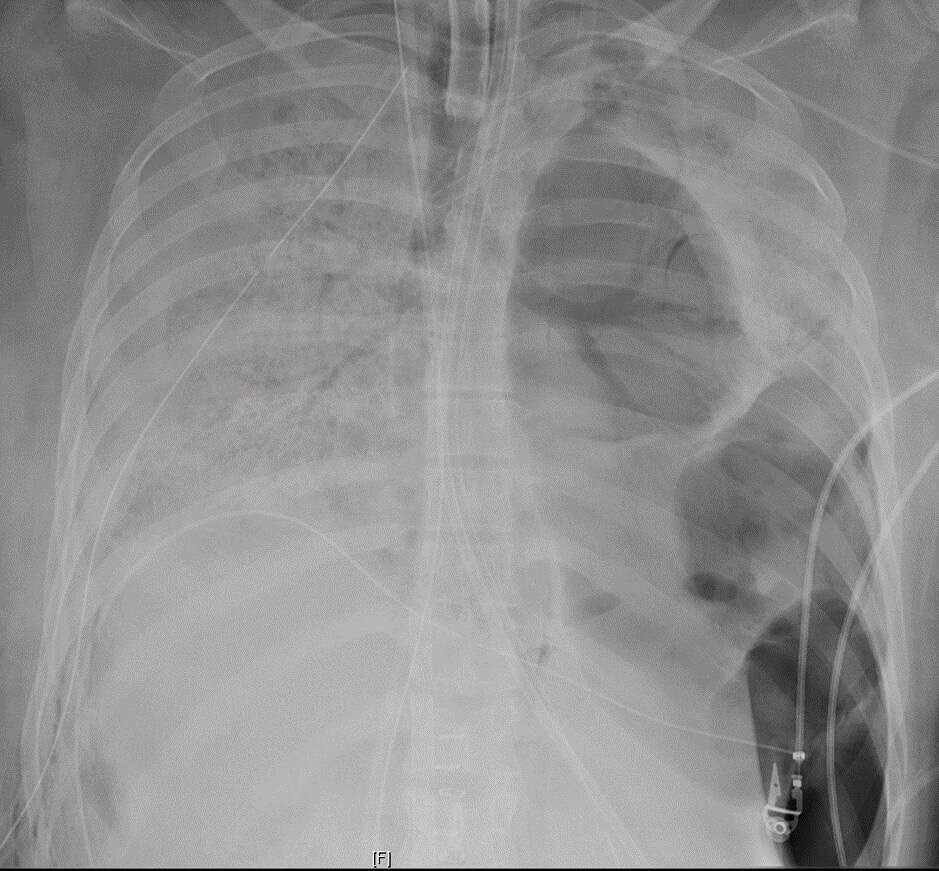

Eventually, the patient’s Covid-19 tests came back negative. Although the virus had been cleared from the body, she remained in severe condition and the lungs were left with irreversible damage from the infection. Her doctors said the lungs were pitted with holes and “completely plastered” to the tissue around them. In a last-ditch effort to save her life, the patient was put on the list for a double-lung transplant. A matching donor was quickly identified and within 48 hours, a team of surgeons performed the 10-hour procedure at Northwestern Memorial Hospital. The operation has been hailed as a success, but this patient’s battle isn’t over yet.

A common symptom of COVID-19 patients is ARDS(Acute Respiratory Distress Syndrome), which is when the lungs are damaged, causing fluids(such as mucus, saliva, blood, etc.) to leak into the alveoli, which are like tiny air sacs. Alveoli are the sites for gaseous exchange, and since the alveoli are flooded with the fluids, the patient faces a shortness of breath.